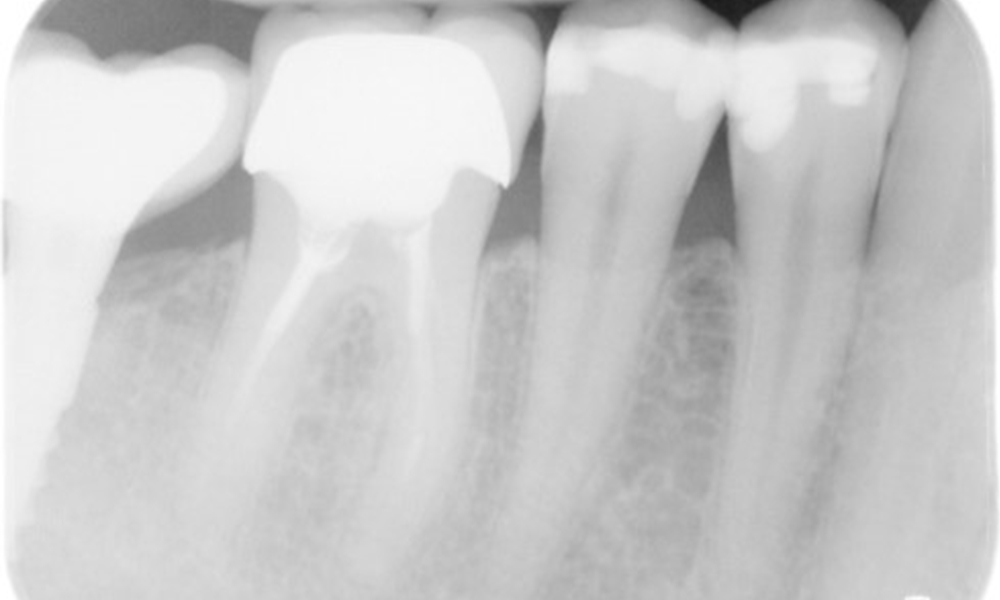

In the medical history, the 55-year-old patient states that he has no systemic disease and is not taking any medication. The patient’s lifestyle is similarly unremarkable. The patient has a few tooth restorations and two implants (2nd and 4th quadrants). On the basis of current findings, gingivitis is identified in an otherwise stable periodontal condition on the reduced periodontium (stage III, grade A).

Previous treatments: dental restorations (non-precious metal/ceramic blend), two implants (2nd, 4th quadrants)

The patient has no particular risk factors with specific dental implications. The key factor, therefore, is the requirement in terms of oral health. In this respect, good oral health is evident with stable, reduced periodontium. Should evidence of an increase in probe depth compared with the baseline, combined with diffuse bleeding, be found at a check-up appointment, diagnosis using X-ray imaging (dental X-ray) should be undertaken in order to identify peri-implant bone loss at an early stage and intervene accordingly.